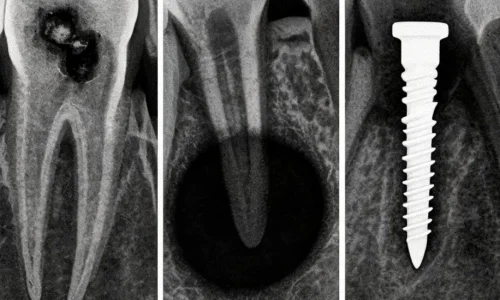

Стоматологический снимок для пациента часто выглядит как серо-белая схема, где трудно отличить корень от пломбы, а нормальную тень — от проблемы. Врач видит в нём гораздо больше: контактные поверхности между зубами, края старых реставраций, состояние каналов, костную ткань вокруг корней, положение зубов мудрости, высоту кости перед имплантацией и мелкие изменения, которые ещё не дают боли. Именно поэтому снимок нередко становится моментом, когда скрытая проблема впервые становится видимой.

После этого нейросеть ищет признаки, на которых её обучали. Для кариеса это могут быть тёмные участки в эмали и дентине, особенно между зубами и под старыми пломбами. Для кист и воспалений важны изменения костной ткани около корня. Для имплантации система может помогать оценивать высоту и объём кости, расстояние до важных анатомических структур и общее состояние зоны, где планируется установка импланта.

Кариес: почему AI полезен на ранних стадиях

Кариес не всегда начинается с заметной дырки или боли. Он может развиваться между зубами, под краем пломбы или в зоне, которую трудно хорошо рассмотреть при обычном осмотре. Пациент может ничего не чувствовать, а на снимке уже появляется слабое изменение плотности тканей.

Нейросети полезны именно в таких случаях. Они помогают обратить внимание на небольшие затемнения, которые могут указывать на начальное поражение. Особенно это важно на bitewing-снимках, где хорошо видны контактные поверхности зубов. Если ранний кариес заметить вовремя, лечение может быть менее объёмным: иногда достаточно наблюдения, реминерализации, коррекции гигиены или небольшой реставрации, а не сложного восстановления после глубокого разрушения.

Но у AI есть ограничение. Затемнение на снимке не всегда означает активный кариес, требующий немедленного сверления. Врач должен оценить глубину поражения, состояние эмали, риск пациента, гигиену, питание, сухость во рту, старые пломбы и динамику. Поэтому нейросеть помогает увидеть подозрительный участок, но не должна превращать каждый сигнал в автоматическое лечение.

Кисты и воспаления у корня

Киста, гранулёма или хроническое воспаление у верхушки корня могут долго не беспокоить пациента. Иногда зуб не болит, десна выглядит спокойно, а проблема обнаруживается случайно — на снимке перед лечением, протезированием или имплантацией. Такие изменения особенно важно не пропустить, потому что воспаление может увеличиваться, разрушать костную ткань и осложнять дальнейшее лечение.

На рентгене и КЛКТ врач ищет зоны разрежения кости около корня, изменение контура, расширение периодонтальной щели и другие признаки. Нейросеть может подсветить подозрительную область и помочь быстрее заметить патологию, особенно если снимков много или изменения небольшие.